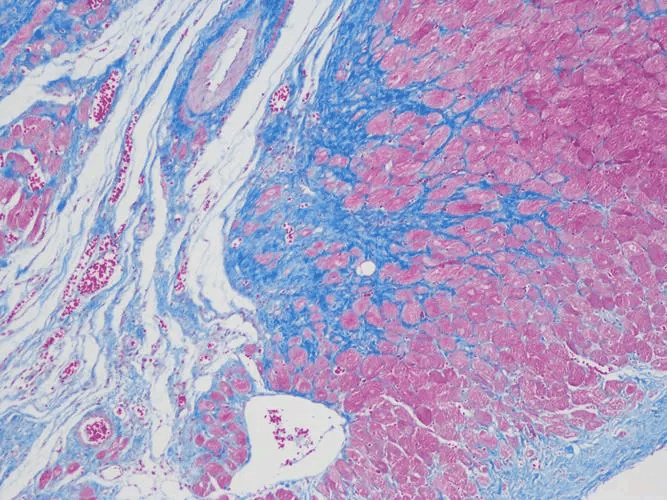

Masson三色染色法

编辑Masson’s trichrome 是一种用于组织学的三色染色程序。 从 Claude L. Pierre Masson(1880-1959)的原始配方演变而来的配方具有不同的具体应用,但都适用于区分细胞与周围结缔组织。

大多数配方会产生红色角蛋白和肌肉纤维、蓝色或绿色胶原蛋白和骨骼、浅红色或粉红色细胞质以及深棕色至黑色细胞核。

标准应用:Masson三色染色法广泛用于研究肌肉病变(肌营养不良)、心脏病(梗死)、肝病变(肝硬化)或肾病变(肾小球纤维化)。 它还可用于检测和分析肝脏和肾脏活组织检查中的肿瘤。